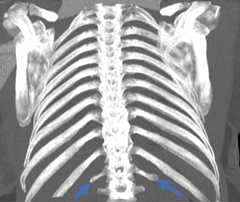

Hypoplastic rib prevalence was found as 10.27%. There were hypoplastic ribs in 115 (52.04%) cases, and their mean age was 52.67. In 2 cases, the first rib was hypoplastic; both were male and on the left side. In 113 cases (51 male, 62 female), the 12th ribs were hypoplastic. Ninety-eight cases had bilateral hypoplastic 12th rib, while 15 (7 on the right, 8 on the left) had unilateral (Table 5). The mean length of all hypoplastic 12th ribs was found to be 3.98 ± 1.58 cm on the left side and 4.00 ± 1.35 cm on the right (p > 0.05; Fig. 7).

Figure 7.Bilateral hypoplastic 12th rib.

Absent rib prevalence was found as 3.84%. There were missing ribs in 43 (19.46%) cases (9 male, 34 female), and their mean age was 54.9. Eleven ribs were observed bilaterally in 36 cases and unilaterally in 7 (3 on the right, 4 on the left). The absent rib in all males was bilateral (Table 5).

Rib spurs extending from the left 11th rib to the 11th intercostal space were observed in 1 (0.45%) case. The case was a 61-year-old male (Fig. 7). The same subject had a comorbidity of fusion anomaly between the 5th and 6th ribs and between the 7th and 8th ribs.

Figure 8.Spurs on the left 11th rib on the coronal computed tomography image (A) and three-dimensional image (B).